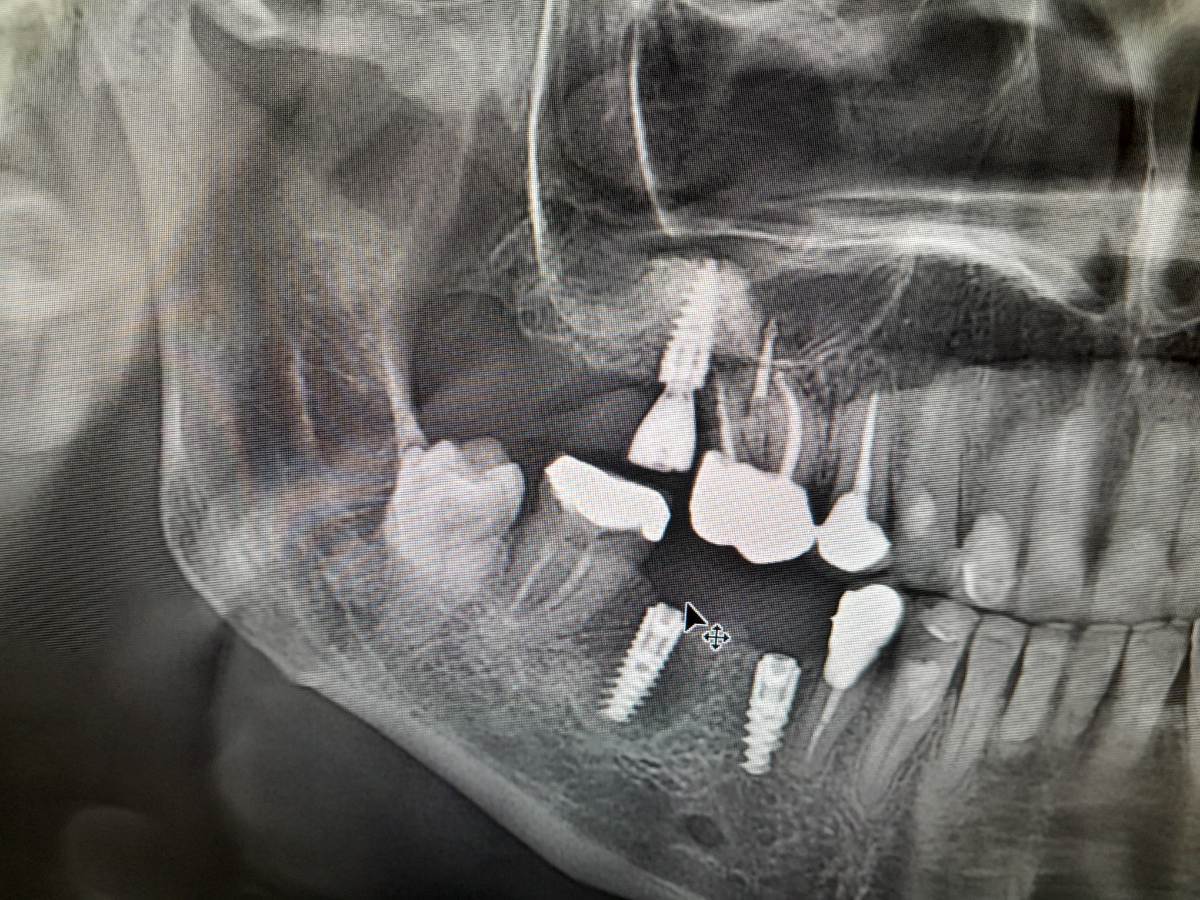

Irina xyz Опубликовано 20 часов назад Автор Поделиться Опубликовано 20 часов назад Это более общий план Имплант на 45м - 3.5 мм диаметр, 10 - длина Ссылка на комментарий

Женька Опубликовано 11 часов назад Поделиться Опубликовано 11 часов назад Здравствуйте. Вопросов к 4.4 и 4.3 много. Но сомневаюсь, что именно 4.3 стал беспокоить на фоне установленного имплантата. Скорее так совпало🤷♂️ Ссылка на комментарий

Irina xyz Опубликовано 1 час назад Автор Поделиться Опубликовано 1 час назад Я могу ошибаться в номерах, но вопрос про первый после импланта зуб, он же резец .. следующий живой не беспокоит никак. Имплант встал оч близко от корня соседа. Сосед стал отзываться при постукивании, но боль уходит при давлении на зуб... Стоит ли переделывать (если надо я лучше заплачу, чем ждать когда оно стнет хуже) или ситуация нормальна и трогать не стоит? Зы: я оч благодарна своим врачам и понимаю какую сложную работу они делают, этот вопрос попытка понять чего ожидать - на основании вашей практики Ссылка на комментарий